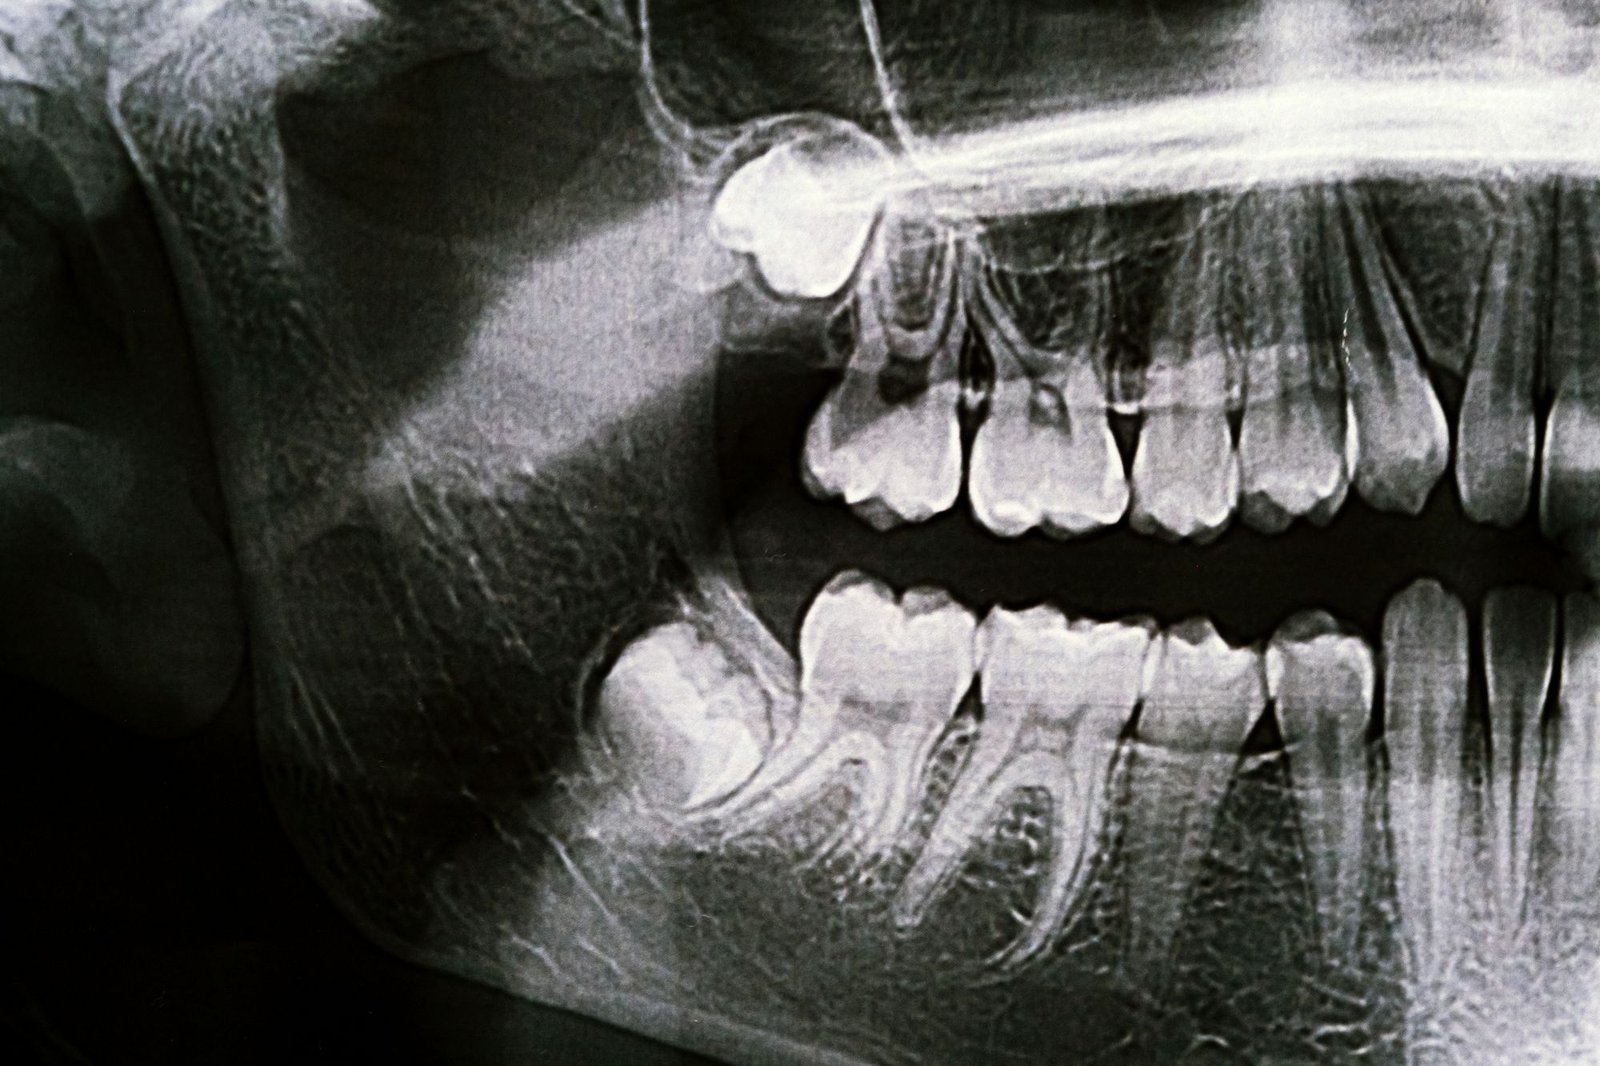

Estos alineadores están fabricados con materiales transparentes y biocompatibles que se ajustan perfectamente a la dentadura, moviendo los dientes de forma gradual y controlada. Gracias a la odontología digital, el paciente puede incluso ver una simulación del resultado final antes de empezar el tratamiento.

En Clínica RAdental, somos especialistas en tratamientos de alineadores que combinan estética, precisión y rapidez. Nuestro equipo planifica cada caso mediante escaneado intraoral y software 3D, garantizando resultados naturales y seguros.